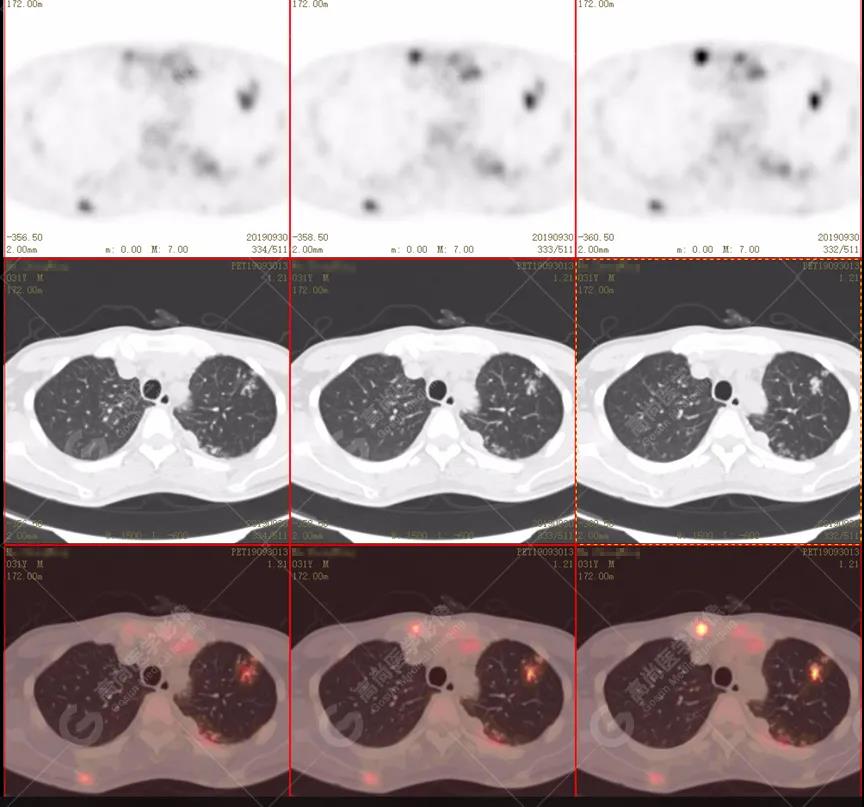

左肺上葉尖后段及下葉背段多發(fā)簇狀斑點狀高代謝灶

左側胸膜結節(jié)樣增厚,代謝不同程度增高

雙肺、左側胸膜多發(fā)結節(jié)影,全身多處骨質破壞,全身多發(fā)淋巴結腫大,代謝攝取不均勻性增高。

2.全身多系統(tǒng)、多形態(tài)、多發(fā)病灶(肺部、胸膜、淋巴結、骨),18F-FDG攝取不均性增高;

特征:肺部病灶簇狀分布,上葉尖段及下葉背段為著;腫大淋巴結分布不對稱,無融合、中央有壞死改變,與淋巴瘤、轉移瘤等有一定的鑒別診斷意義;